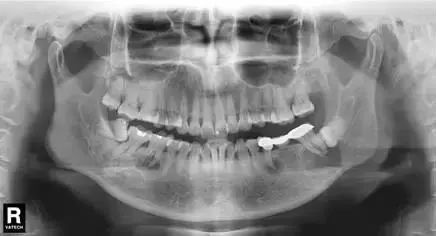

相信大部分的人和小编一样,没等看到具体病情就已经被图中这个巨大的“球”状物体吓到。小小的下巴竟能长出这么大的“球”!

“患者是30多岁的年轻男子,红色标记那颗牙松动,要求拔牙,开始嫌麻烦不愿拍片,后来经过再三劝说还是拍了片。 结果把所有人包括他自己都吓了一跳。 估计是良性,具体还得去医院住院手术做病理检查,所以大家不要忽视一张片子带来辅助检查的重要性。”

试想,如果没有拍片,直接贸然拔牙,一旦出现问题......

一张牙片,“救了”诊所,也“救了”患者!